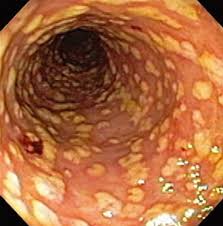

• What is Pseudo Membranous Colitis?

• Pseudo membranous colitis is inflammation of the colon that occurs in some people who have taken antibiotics.

• Pseudo membranous colitis is sometimes called antibiotic-associated colitis or C. difficile colitis.

• The inflammation in pseudo membranous colitis is almost always associated with an overgrowth of the bacterium Clostridium difficile.

• Colonoscopy